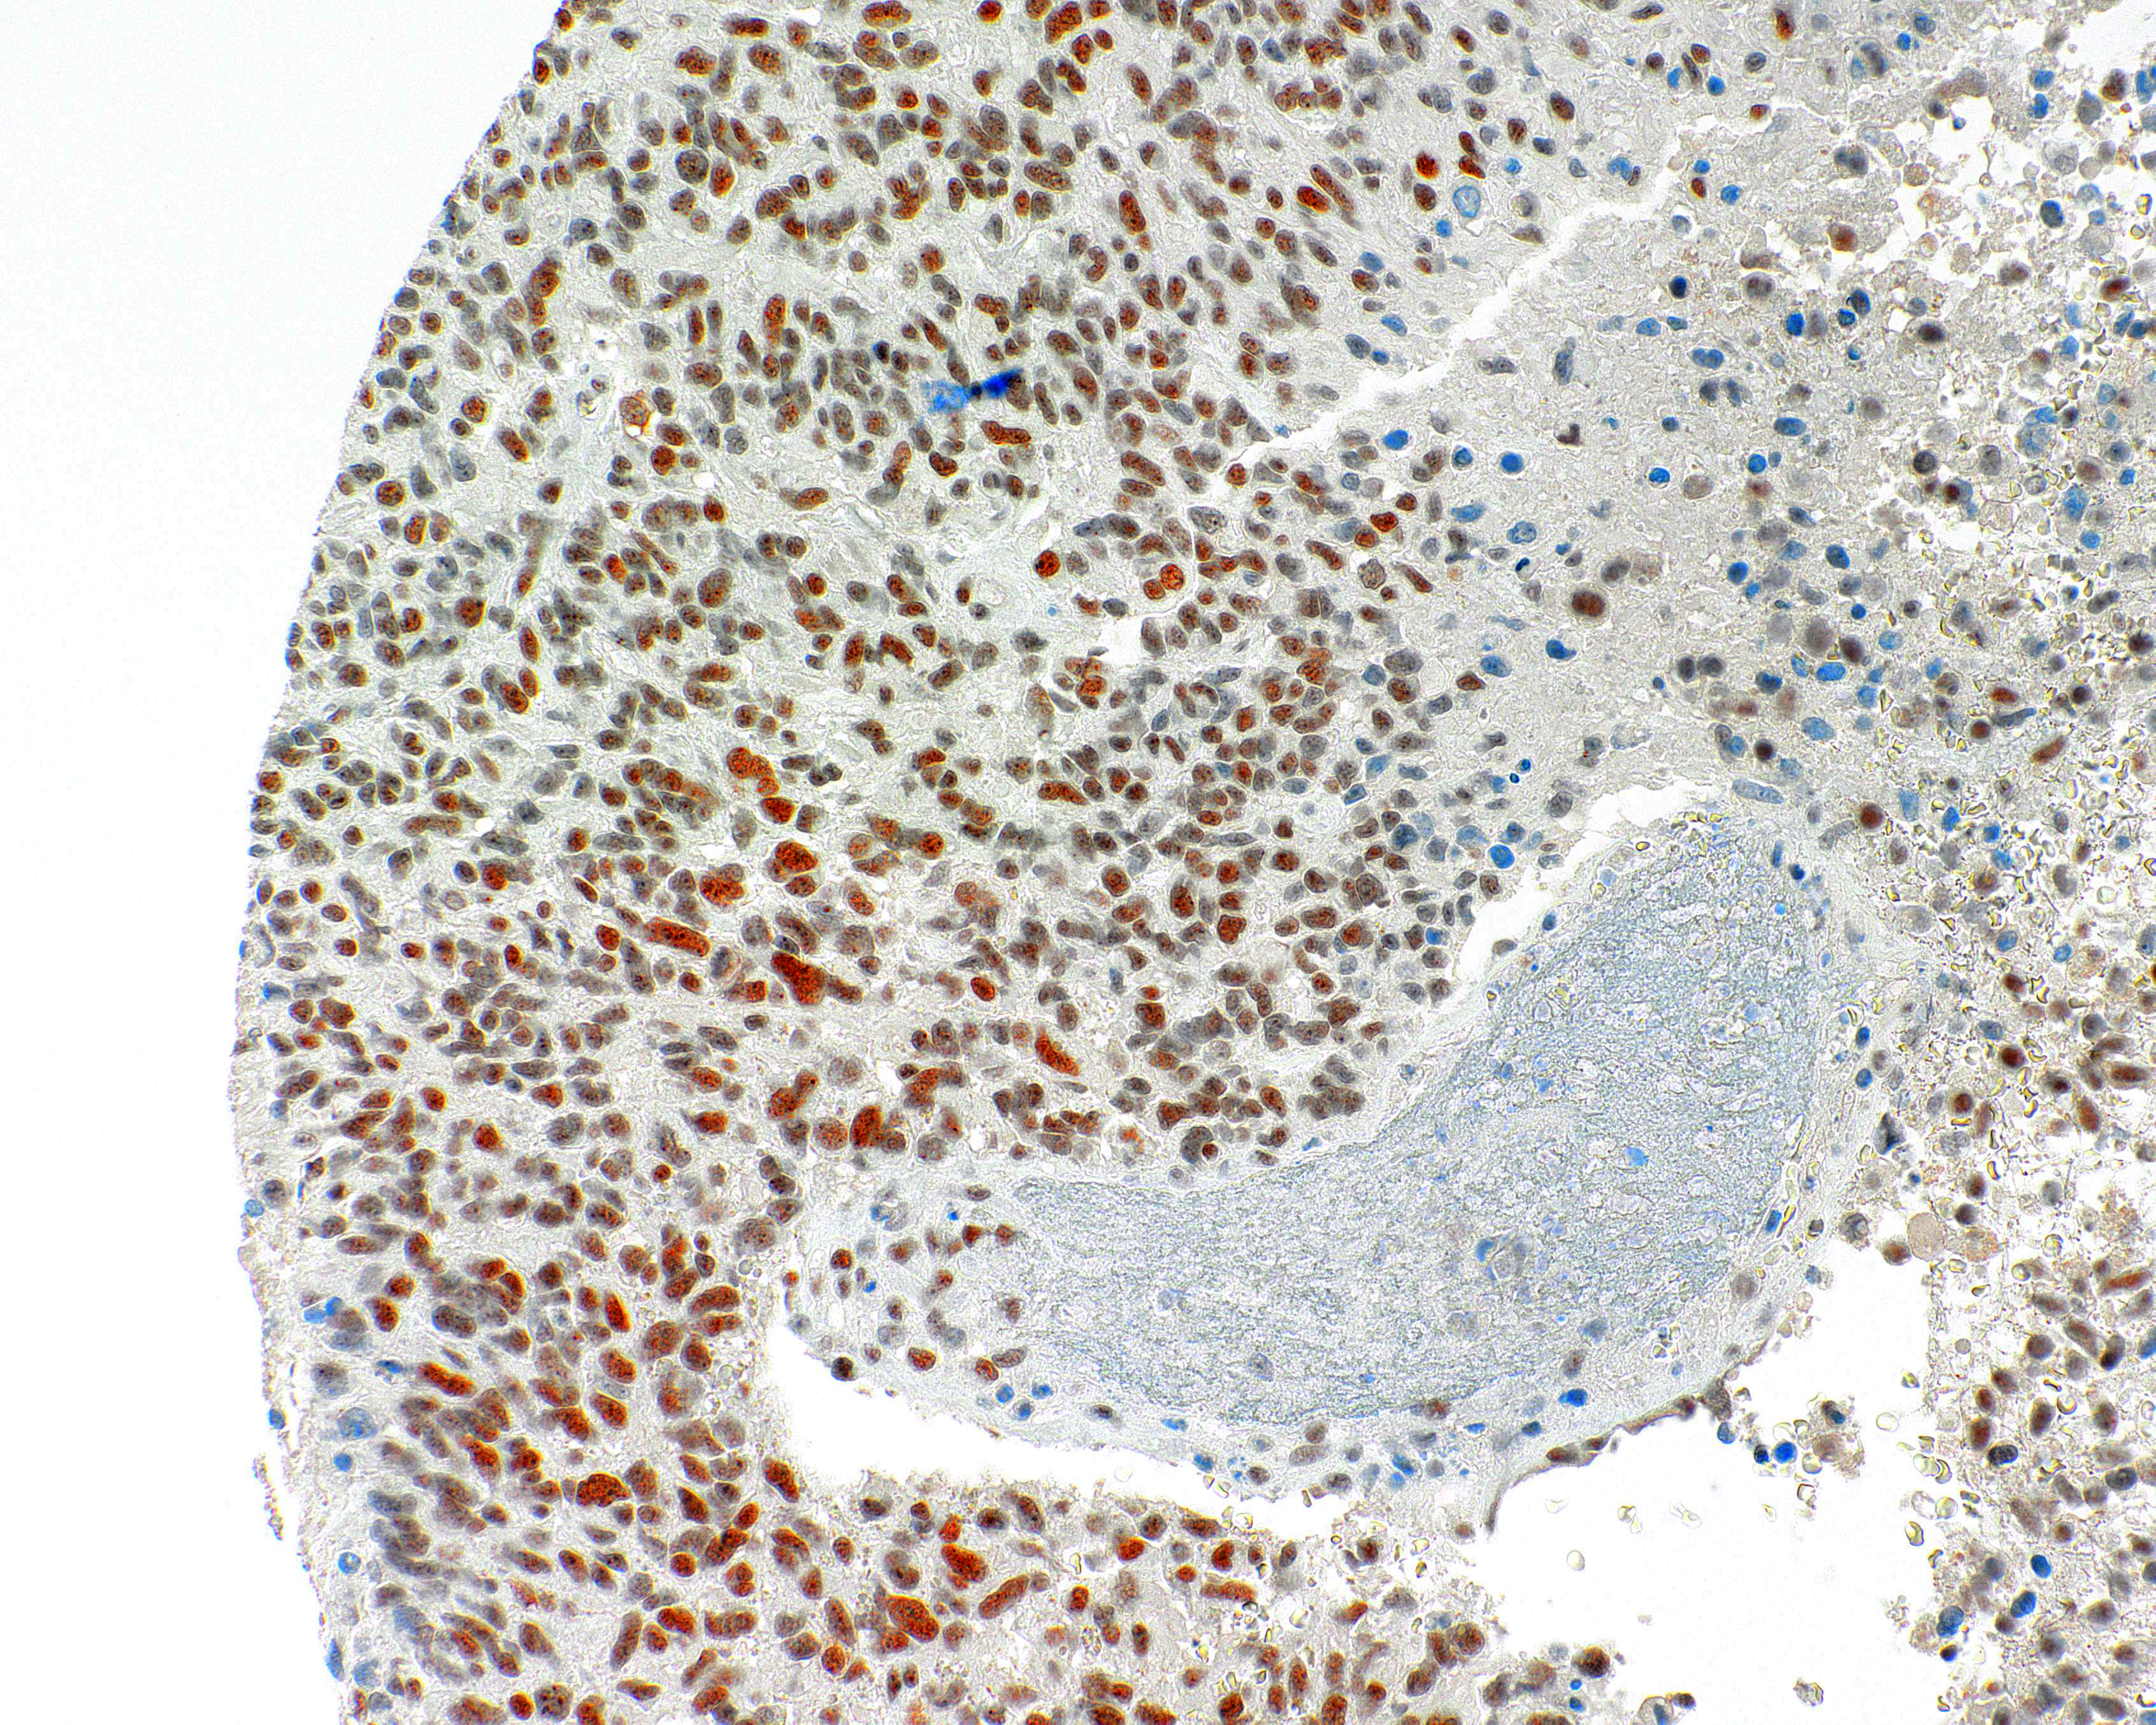

POSITIVE CONTROL:

Glioma

ATRX is involved in the remodeling of the nucelosome structure, and facilitate the transcription and replication. ATRX loss occurs in grades II/III astrocytomas and glioblastomas and comes together with IDH1 mutations. Detection of ATRX with IHC acts a sensitive method to identify the mutations.